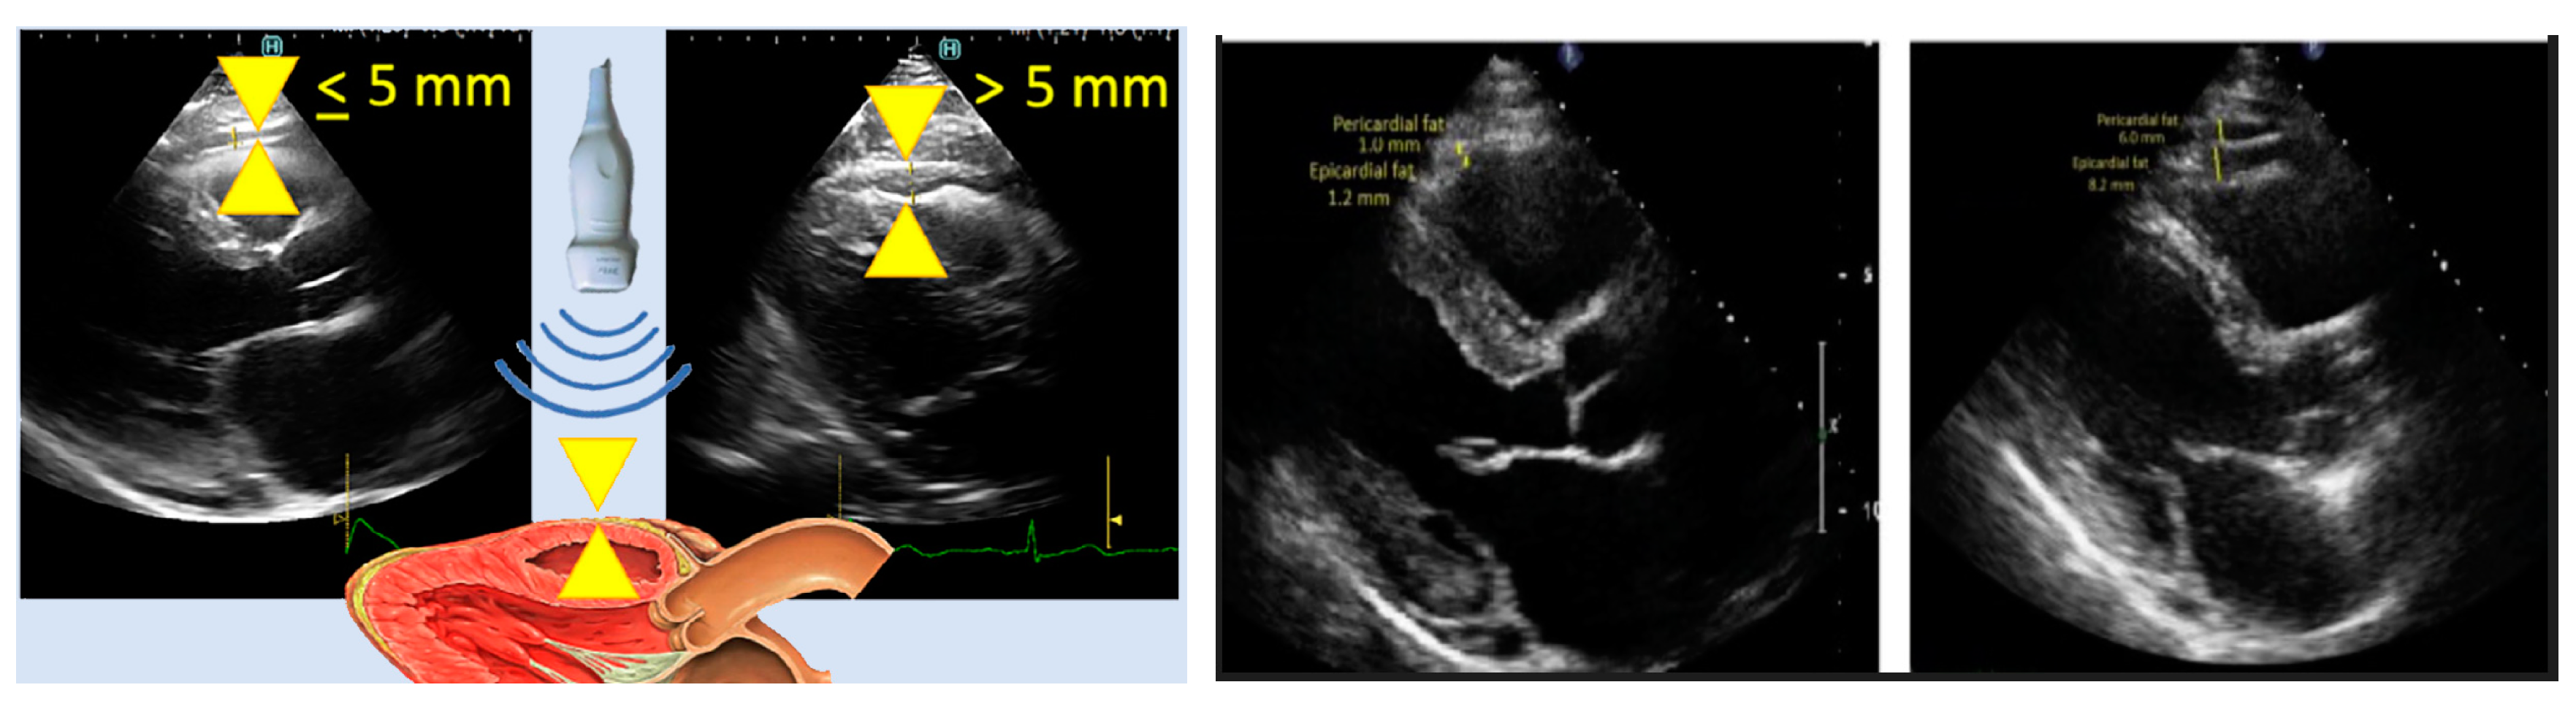

- Iacobellis G, Willens HJ. Echocardiographic Epicardial Fat: A Review of Research and Clinical Applications. Journal of the American Society of Echocardiography. 2009;22(12):1311-1319. [CrossRef]

- Cuellar JR, Gillette L, Dinh V, Woodard P, Burri M, Klingensmith JD. Echocardiogram image segmentation and cardiac adipose tissue estimation using spectral analysis and deep learning. Proc SPIE 12932, Medical Imaging 2024: Ultrasonic Imaging and Tomography. Published online April 1, 2024. [CrossRef]

- Klingensmith JD, Karlapalem A, Kulasekara MM, Fernandez-del-Valle M. Spectral analysis of ultrasound radiofrequency backscatter for the identification of epicardial adipose tissue. J Med Imag. 2022;9(01). [CrossRef]

- Iacobellis G, Willens HJ, Barbaro G, Sharma AM. Threshold values of high-risk echocardiographic epicardial fat thickness. Obesity (Silver Spring). 2008;16(4):887-892. [CrossRef]